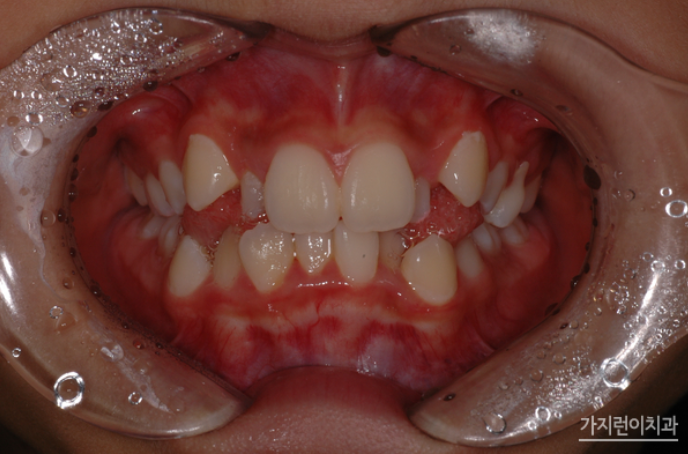

유독 송곳니 덧니가 심한데...

치아가 맹출하는 순서상 송곳니가 가장 마지막에 맹출하기 때문에 송곳니 자리에 덧니가 많이 생기는데요. 이렇게 덧니가 생기게 되면 위의 사진에서 보이는 악궁확장장치를 이용하여 입 천장의 뼈를 좌우로 벌려 덧니가 올바로 자리를 잡을 수 있는 공간을 확보하여 진행하게 됩니다. 이런 덧니는 빈번하게 일어나는 현상인데요. 유치가 빠지지 않는 맹출장애의 경우도 치과를 방문해 검진을 받아보는 게 좋습니다.